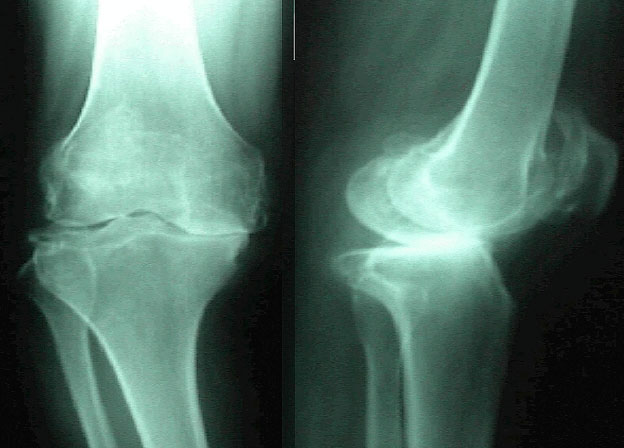

減慢腰及膝蓋關節退化

年齡的增長,加上日積月累的操勞工作,退化的問題就像呼吸一樣來得自然,勞損愈多,關節退化就愈快。想要減慢腰部和膝蓋關節退化的速度,可做的事情有很多,其中之一,就是要養成隨時保持正確姿勢的習慣,然後要記住如何維持不讓關節過度受壓的姿勢。